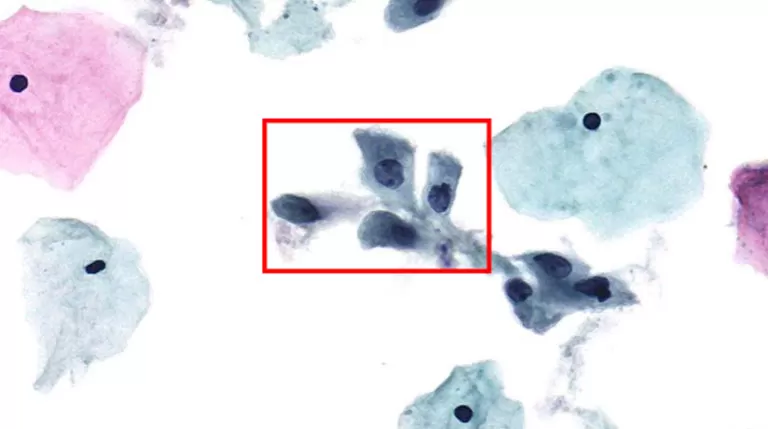

Figure 1: Typical HSIL Morphology Note: Prepared via HealthSky SCTE-3600A SCT Method; Reviewed with HealthSky Patho. AI-Assisted Diagnostic System.

Cells may occur singly, but typically present in "crowded sheets" or "syncytial-like" aggregates with indistinct cell borders.

Chromatin: May be fine or coarsely granular, but is uniformly distributed.

Nuclear Membrane: Distinctly irregular contours, often with prominent indentations or notches.

Nucleoli: Generally absent, though occasionally observed, particularly when HSIL involves endocervical gland spaces or occurs in a background of reactive/reparative changes.

Displays varied morphology; may appear "immature," delicate/lace-like, or present as dense metaplastic staining. Occasionally, cytoplasm may appear "mature" with dense keratinization (Keratinizing HSIL).